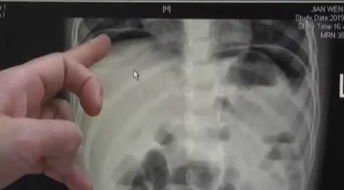

婴儿肠坏死是一种影响婴儿小肠的疾病,通常是因为小肠的血液供应不足,导致部分或全部小肠死亡。这种疾病通常发生在早产儿和出生体重较低的婴儿身上,但也可能发生在其他健康的婴儿身上。婴儿肠坏死是一种非常危险的疾病,如果不及时治疗,婴儿可能会死亡。

3.挽救婴儿肠坏死的方法

挽救婴儿肠坏死的方法取决于疾病的严重程度。如果疾病较轻,通常可以通过改变婴儿的饮食和药物治疗来治疗。但是,对于重症患者,可能需要进行手术。

手术通常涉及部分或全部小肠的切除,以帮助婴儿恢复。但是,手术本身也有风险,包括感染和出血。